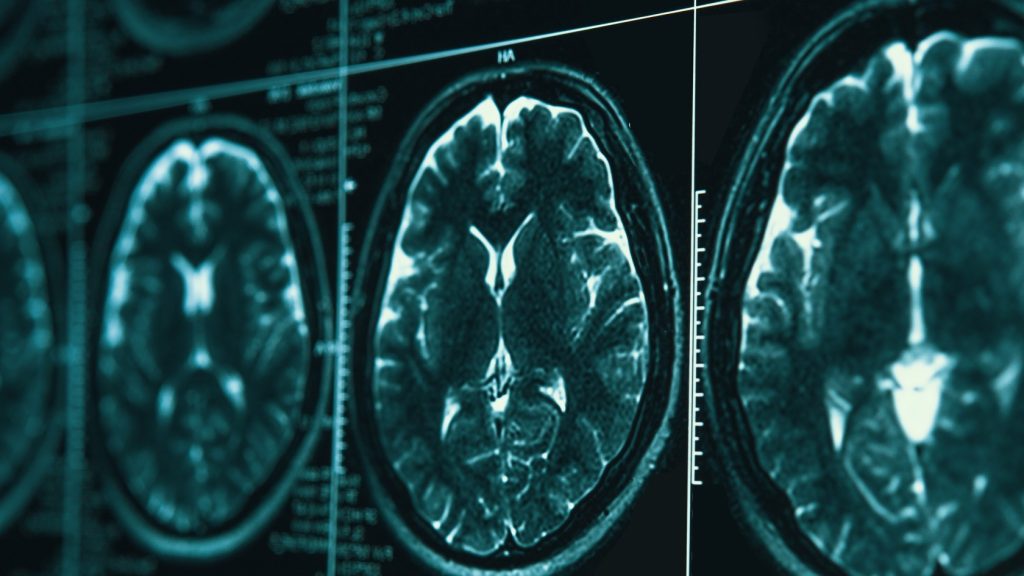

By the time symptoms begin creating problems, the disease has been unfolding in the brain for years. Microscopic amyloid-beta plaques have accumulated between neurons, and later threads of neurofibrillary tau proteins have tangled themselves into tight knots inside brain cells. The two abnormalities — first described in 1906 by the German physician Alois Alzheimer — have become the twin hallmarks of the disease.

But new technologies — artificial intelligence that may be able to identify new genetic determinants of the disease, blood tests for proteins in the brain, and real-time brain monitoring that reveals how individual neurons die — are finding new ways to understand and possibly help treat Alzheimer’s.